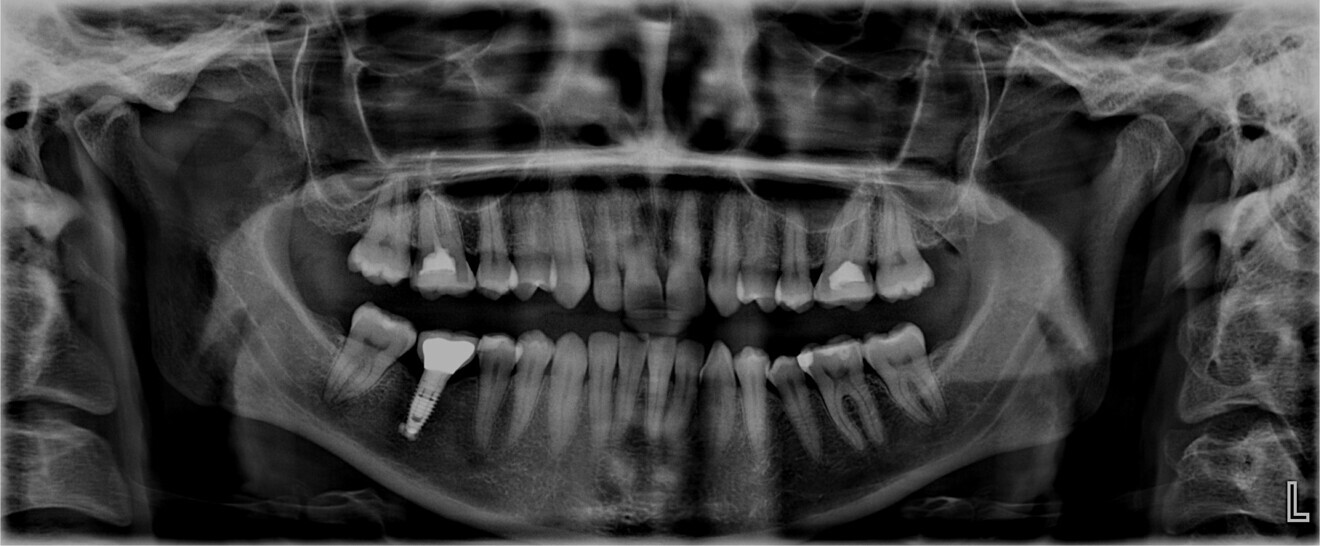

Fig. 3: Pretreatment panoramic radiograph.

The patient had an implant in position #46, whereas teeth #16 and 26 had been endodontically treated. These teeth showed no symptoms; thus, it was decided to re-evaluate the endodontic treatments only if necessary.

The third molars were not present. The evaluation of the cephalometric radiograph (Fig. 4) showed a retrognathic mandible (SNB: 74.2°) and normal inclination of the incisors, both maxillary (Ui–FH: 111.3°) and mandibular (Li–APog: 24.2°).